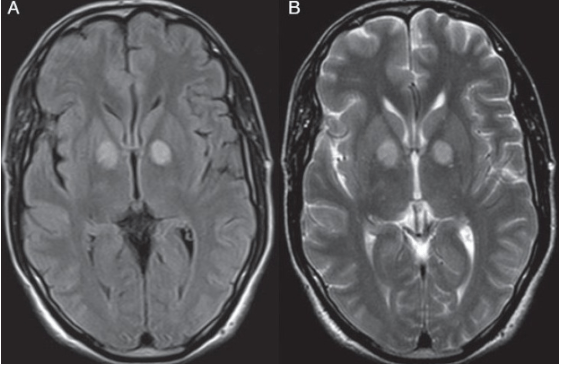

21 y/o M with Type I DM presents with abdominal pain, dehydration, and hyperventilation. DXT=450. After aggressive administration of insulin and fluids, the patient develops altered mental status and seizures. The following MRI is obtained, confirming your suspicion of this syndrome.

What is Osmotic Demyelination Syndrome (previously Central Pontine Myelinolysis)?